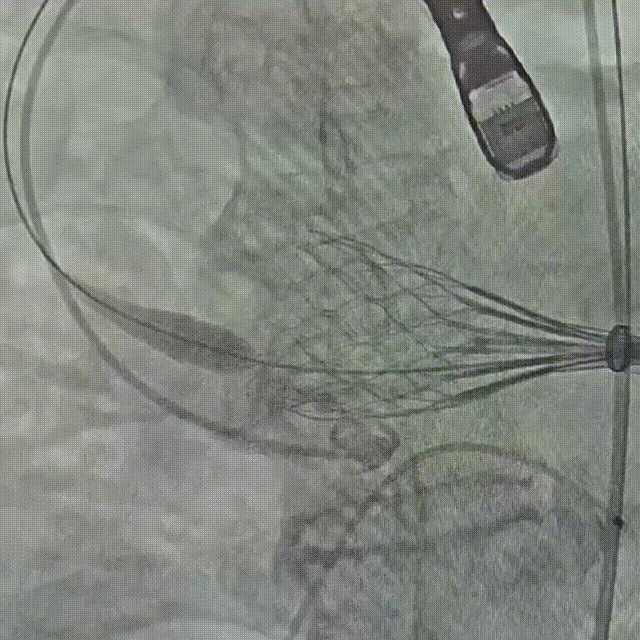

初始造影确定瓣环位置

20mm球囊预扩,无腰有漏;选择27号瓣膜可充分封堵

瓣膜0位定位释放,导丝保持张力,保证同轴性

瓣膜展开后造影评估瓣膜位于0位,无瓣周漏

多角度评估,瓣膜位置可,同轴性佳,可以脱钩释放

脱钩后造影,瓣膜无位移,无瓣周漏